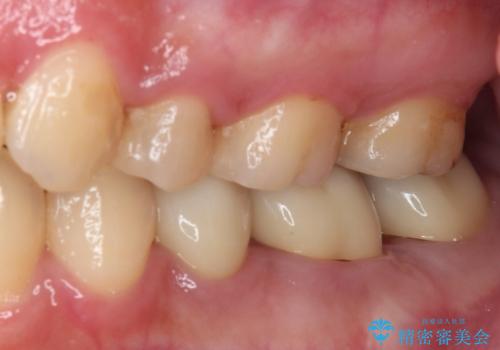

まだ銀歯が残っていますが、大きく目立つ銀歯をセラミックに置き換えることができ、人前で口を開けることを気にしなくなりました。

補綴治療中の後戻り対策をしっかりと行ったことで、歯列全体をきれいに整えることができました。